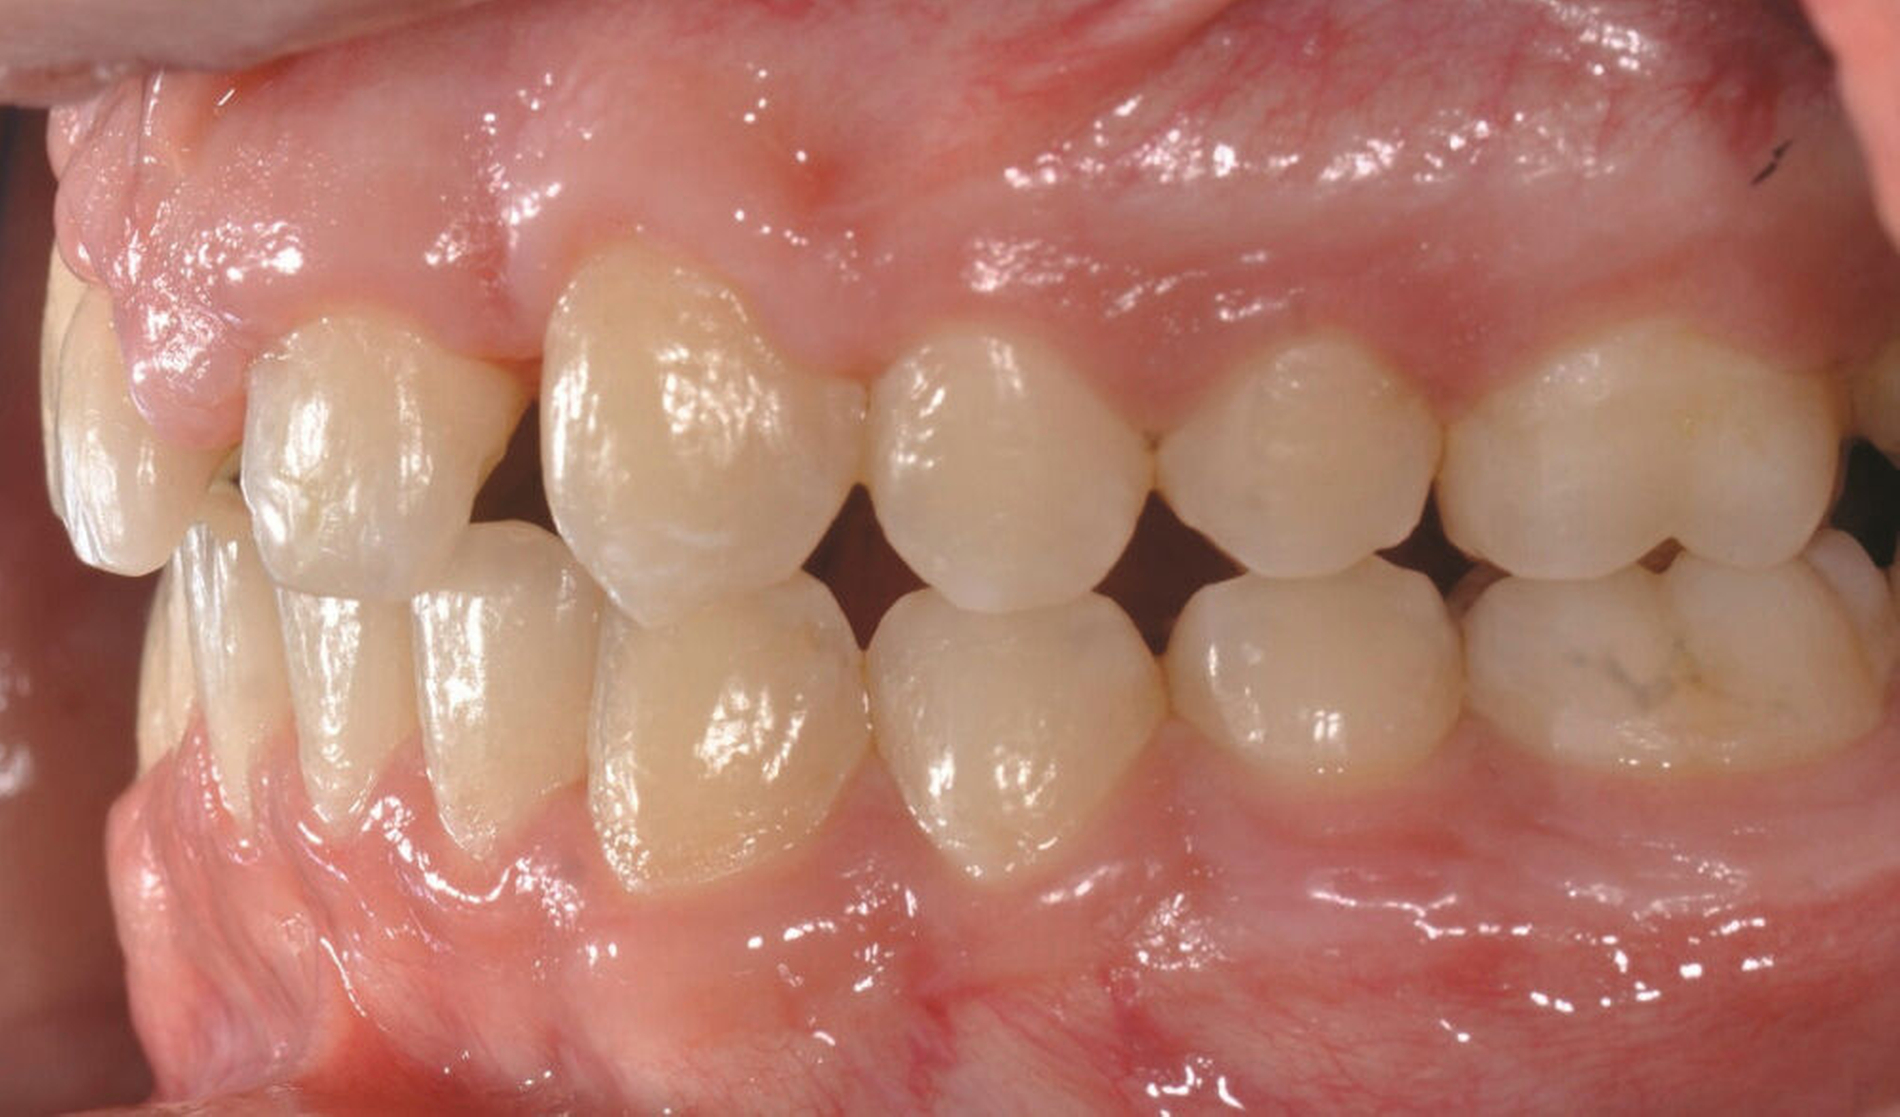

Die direkten und indirekten Kompositrestaurationen werden abschließend mit Skalpellen (Nr. 12), diamantierten Schallspitzen, rotierenden Instrumenten und Soflex-Scheiben ausgearbeitet, in statischer und dynamischer Okklusion kontrolliert, entsprechend eingeschliffen und auf Hochglanz poliert. Die Hygienefähigkeit der marginalen Bereiche wird sichergestellt und dem Patienten werden zur häuslichen Reinigung der Zahnzwischenräume passende Interdentalraumbürstchen angepasst (Abbildung 3).